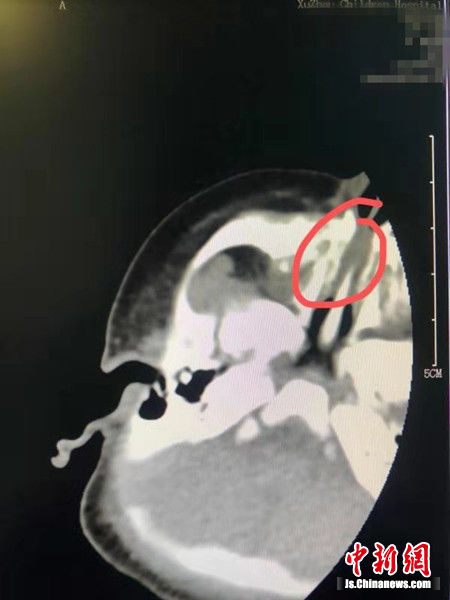

患兒CT檢查結(jié)果。崔玨 攝

不久前,一名出生2天的新生兒由120急救車送到徐州市兒童醫(yī)院,家人表示嬰兒出生后不能正常呼吸。“檢查后發(fā)現(xiàn),嬰兒鼻道狹窄,需要手術(shù)干預(yù)進(jìn)行治療。”紀(jì)堯峰說,嬰兒的CT結(jié)果診斷為“雙側(cè)下鼻甲粘膜增厚,雙側(cè)鼻道不通暢,鼻甲至鼻中隔距離約2.1mm。咽后壁軟組織無增厚。鼻竇內(nèi)見低密度影”。由于孩子出生2天,鼻孔太小,加上身體各項(xiàng)機(jī)能不適合手術(shù),醫(yī)生專門為其制定了一套治療方案。